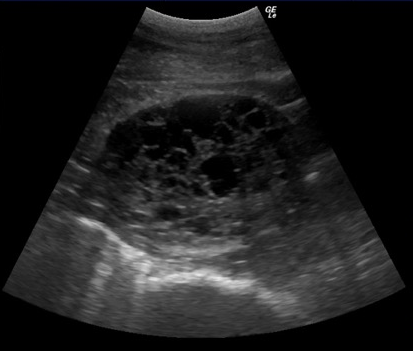

Mit der transrektalen ultrasonographischen Untersuchung können die Eierstöcke dargestellt und ausgemessen werden. Der betroffene Eierstock ist vergrössert und von wabenartiger Struktur (Bild) und der gegenüberliegende Eierstock ist meistens verkleinert.